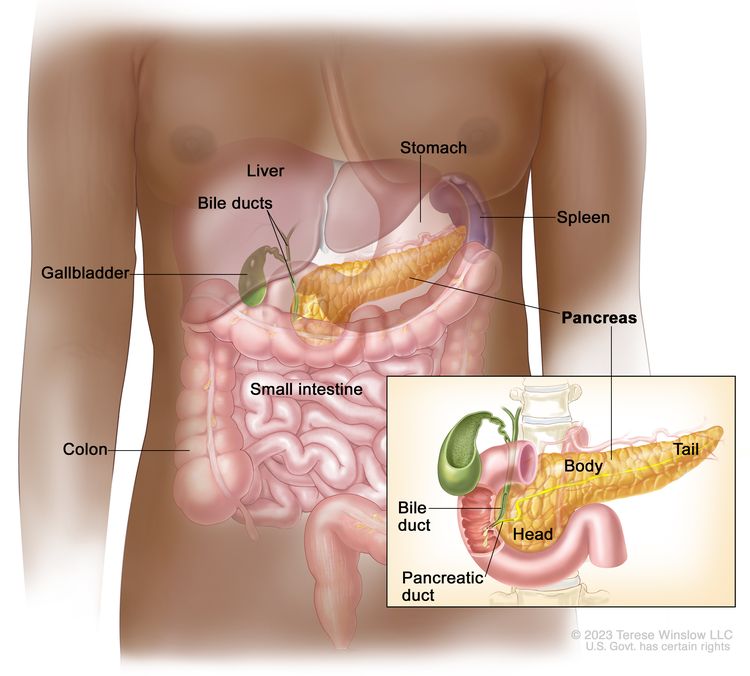

1. Overview

What is Pancreatic Cancer?

Pancreatic cancer is a type of cancer that starts in the pancreas, an organ that plays an important role in digestion and blood sugar control. It develops when pancreatic cells grow abnormally and form a tumor.

Because the pancreas is located deep inside the abdomen, early pancreatic cancer symptoms are often mild or unclear. As a result, pancreatic cancer is frequently diagnosed at a later stage.

2. Where It Begins

Which part of the body is involved?

The pancreas is a small gland located behind the stomach and close to the liver and intestines. It performs two key functions:

● Releases digestive enzymes to help break down food

● Produces hormones such as insulin to regulate blood sugar

Most pancreatic cancers begin in the ducts that carry digestive enzymes.

The pancreas is a small gland located behind the stomach and close to the liver and intestines. It performs two key functions:

● Releases digestive enzymes to help break down food

● Produces hormones such as insulin to regulate blood sugar

Most pancreatic cancers begin in the ducts that carry digestive enzymes.